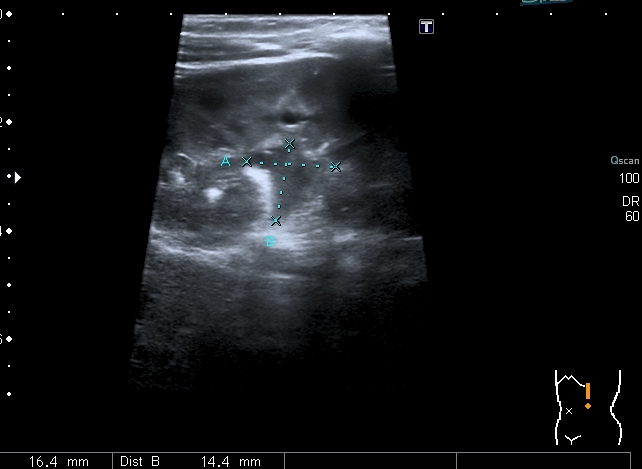

В нижней чашечке левой почки - конкремент до 5 мм

Конкремент даёт твитлинг - артефакт